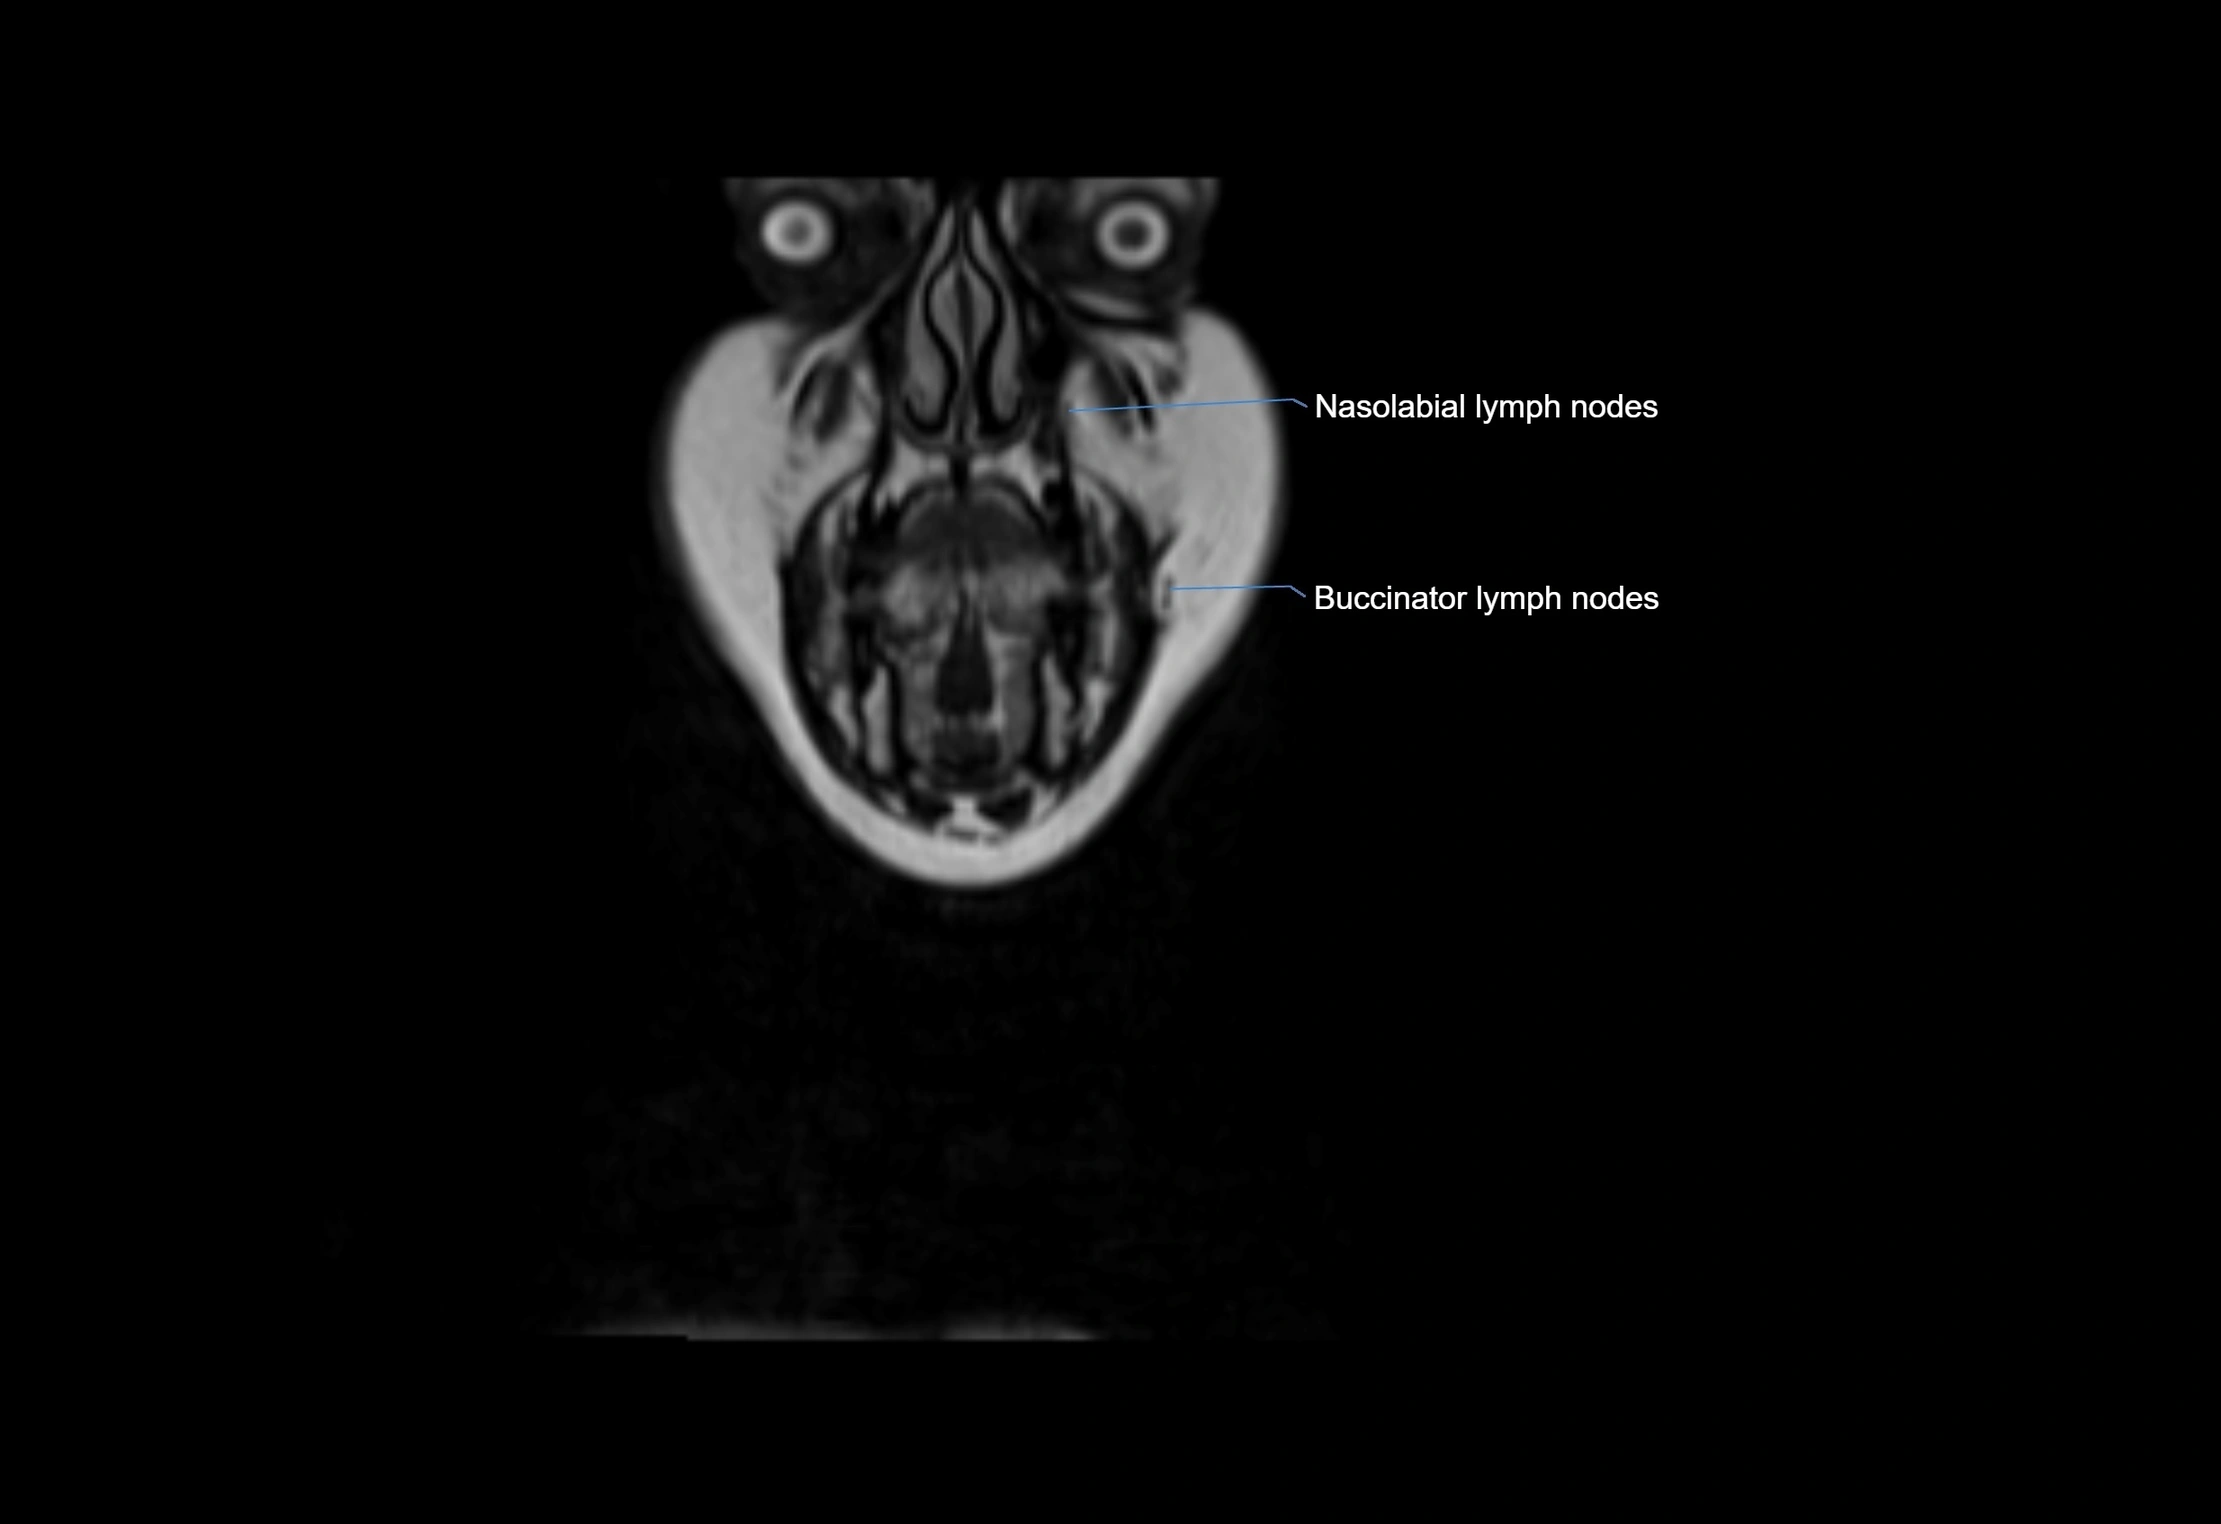

MRI Appearance

T1-weighted images:

• Normal accessory nodes appear as small, oval hypointense to intermediate signal structures within subcutaneous fat

• Surrounded by hyperintense fat, enhancing contrast for visualization

• Pathological nodes may appear enlarged or rounded, sometimes with cortical thickening

T2-weighted images:

• Nodes show intermediate signal, with surrounding fat bright

• Useful for detecting edema, inflammation, or infiltration

• Fatty hilum may appear slightly hyperintense relative to cortex

STIR (Short Tau Inversion Recovery):

• Fat suppression enhances visualization of edematous or pathological nodes

• Normal nodes appear low to intermediate signal, while inflamed or metastatic nodes appear hyperintense

• Useful for detecting subtle lymphadenopathy or early pathology